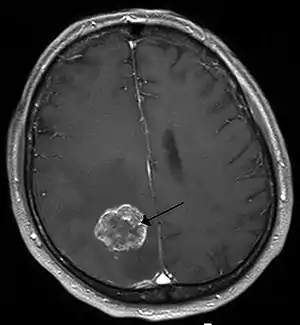

![]() | |

| Brain metastasis in the right cerebral hemisphere from lung cancer, shown on magnetic resonance imaging | |